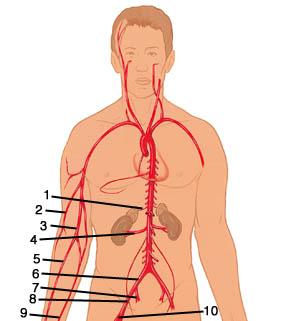

Aortic Arch

Ascending/descending aorta

Axillary artery/vein

Basilar artery

Brachial artery

Brachiocephalic artery

Brachiocephalic vein

Celiac trunk

Common hepatic artery

Common iliac artery/vein

Femoral artery/vein

Gonadal (=testicular/ovarian) artery/vein

Internal/external/common carotid artery

Internal/external iliac artery/vein

Popliteal artery/vein

Radial artery/vein

Renal artery/vein

Splenic artery/vein

Subclavian artery/vein

Superior/inferior mesenteric artery

Superior/inferior vena cava

Thoracic aorta

Abdominal Aorta

Vertebral artery